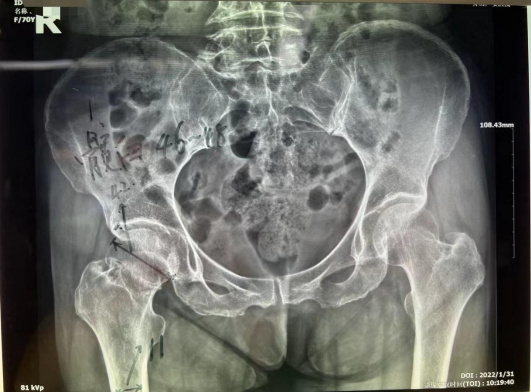

家住普陀的鄭阿姨今年70歲,大年初一在路上行走時不慎被電動車撞倒,右髖部當(dāng)即動彈不得。當(dāng)即被家人送來我院就診。門診拍片診斷為右股骨頸骨折,由于保守治療導(dǎo)致股骨頭壞死、骨折端不能生長的可能性極大。而且長期臥床也容易引發(fā)褥瘡、深靜脈血栓、肺部感染等并發(fā)癥。醫(yī)生建議其行全髖關(guān)節(jié)置換術(shù)。

患者為右股骨頸骨折